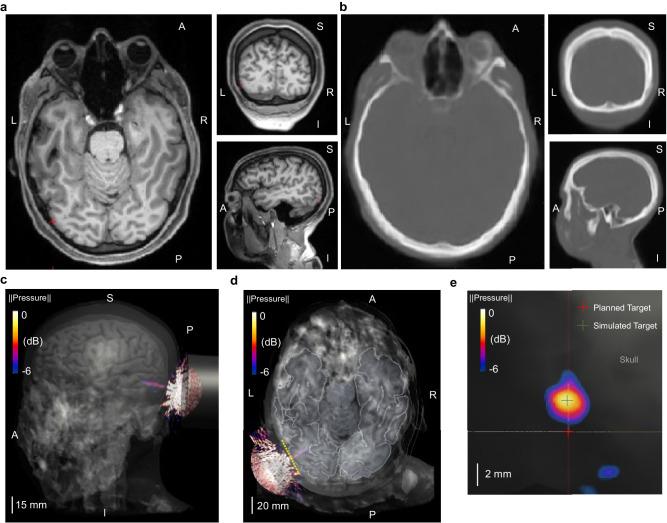

A brain-computer interface (BCI) enables users to control devices with their minds. Despite advancements, non-invasive BCIs still exhibit high error rates, prompting investigation into the potential reduction through concurrent targeted neuromodulation. Transcranial focused ultrasound (tFUS) is an emerging non-invasive neuromodulation technology with high spatiotemporal precision. This study examines whether tFUS neuromodulation can improve BCI outcomes, and explores the underlying mechanism of action using high-density electroencephalography (EEG) source imaging (ESI). As a result, V5-targeted tFUS significantly reduced the error in a BCI speller task. Source analyses revealed a significantly increase in theta and alpha activities in the tFUS condition at both V5 and downstream in the dorsal visual processing pathway. Correlation analysis indicated that the connection within the dorsal processing pathway was preserved during tFUS stimulation, while the ventral connection was weakened. These findings suggest that V5-targeted tFUS enhances feature-based attention to visual motion.